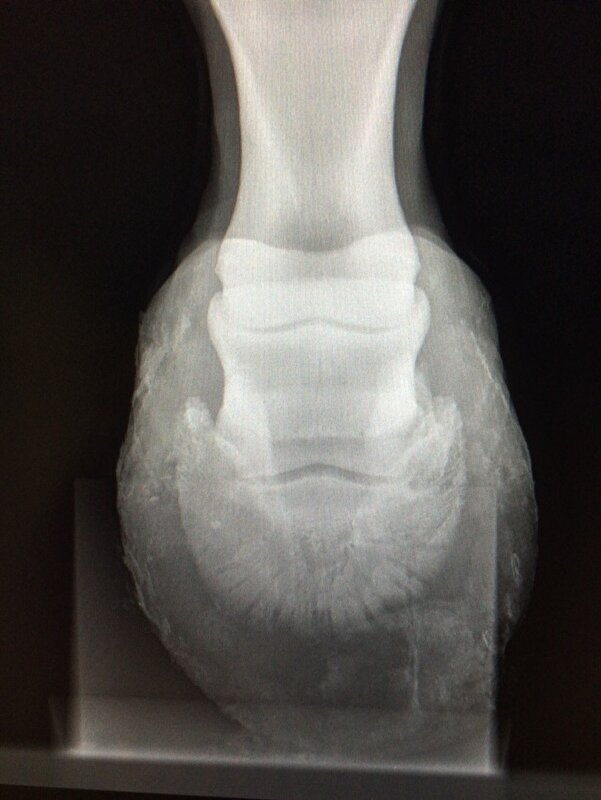

Dus volgens mij werkt het. nuvel schreef:Had gister gebeld maar er was nog niks klaar. Net heb ik de foto's gekregen van beide voorvoeten en het ziet er niet zo goed uit. Beide hoefbenen zijn gekanteld. De ene als je er voor staat is het het linker voorbeen daar komt het hoefbeen bijna door de zool. Als je er voor staat het rechter voorbeen heeft nog een cm voor hij door de zool komt.

Zal straks de rontgenfoto's en foto van het paard hier plaatsen. Ga ze nu eerst naar de kliniek sturen want wil er voor vechten. Dit paard is te sterk en te vrolijk om nu de handdoek in de ring te gooien. Ze staat op dubbele pijnstiller om nu niet te hoeven lijden.